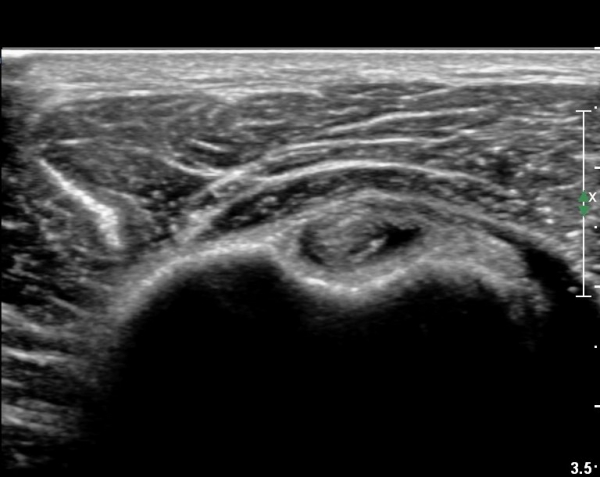

°ß°©ÇÏ±Ù°Ç »óºÎ Á¾´Ü¸é°Ë»ç¿¡¼­ °ß°©ÇϱٰǠ ÆÄ¿­ÀÌ ¶Ñ·ÈÇÔ(»çÁø 4, 5).

ÀÌµÎ¹Ú±Ù°Ç Á¾´Ü¸é°Ë»ç¿¡¼­ Á¡¾×³¶³» ¼ö¾×Àú·ù¿Í °üÀý³» ¼ö¾×Àú·ù°¡ °üÂûµÊ(»çÁø 6).